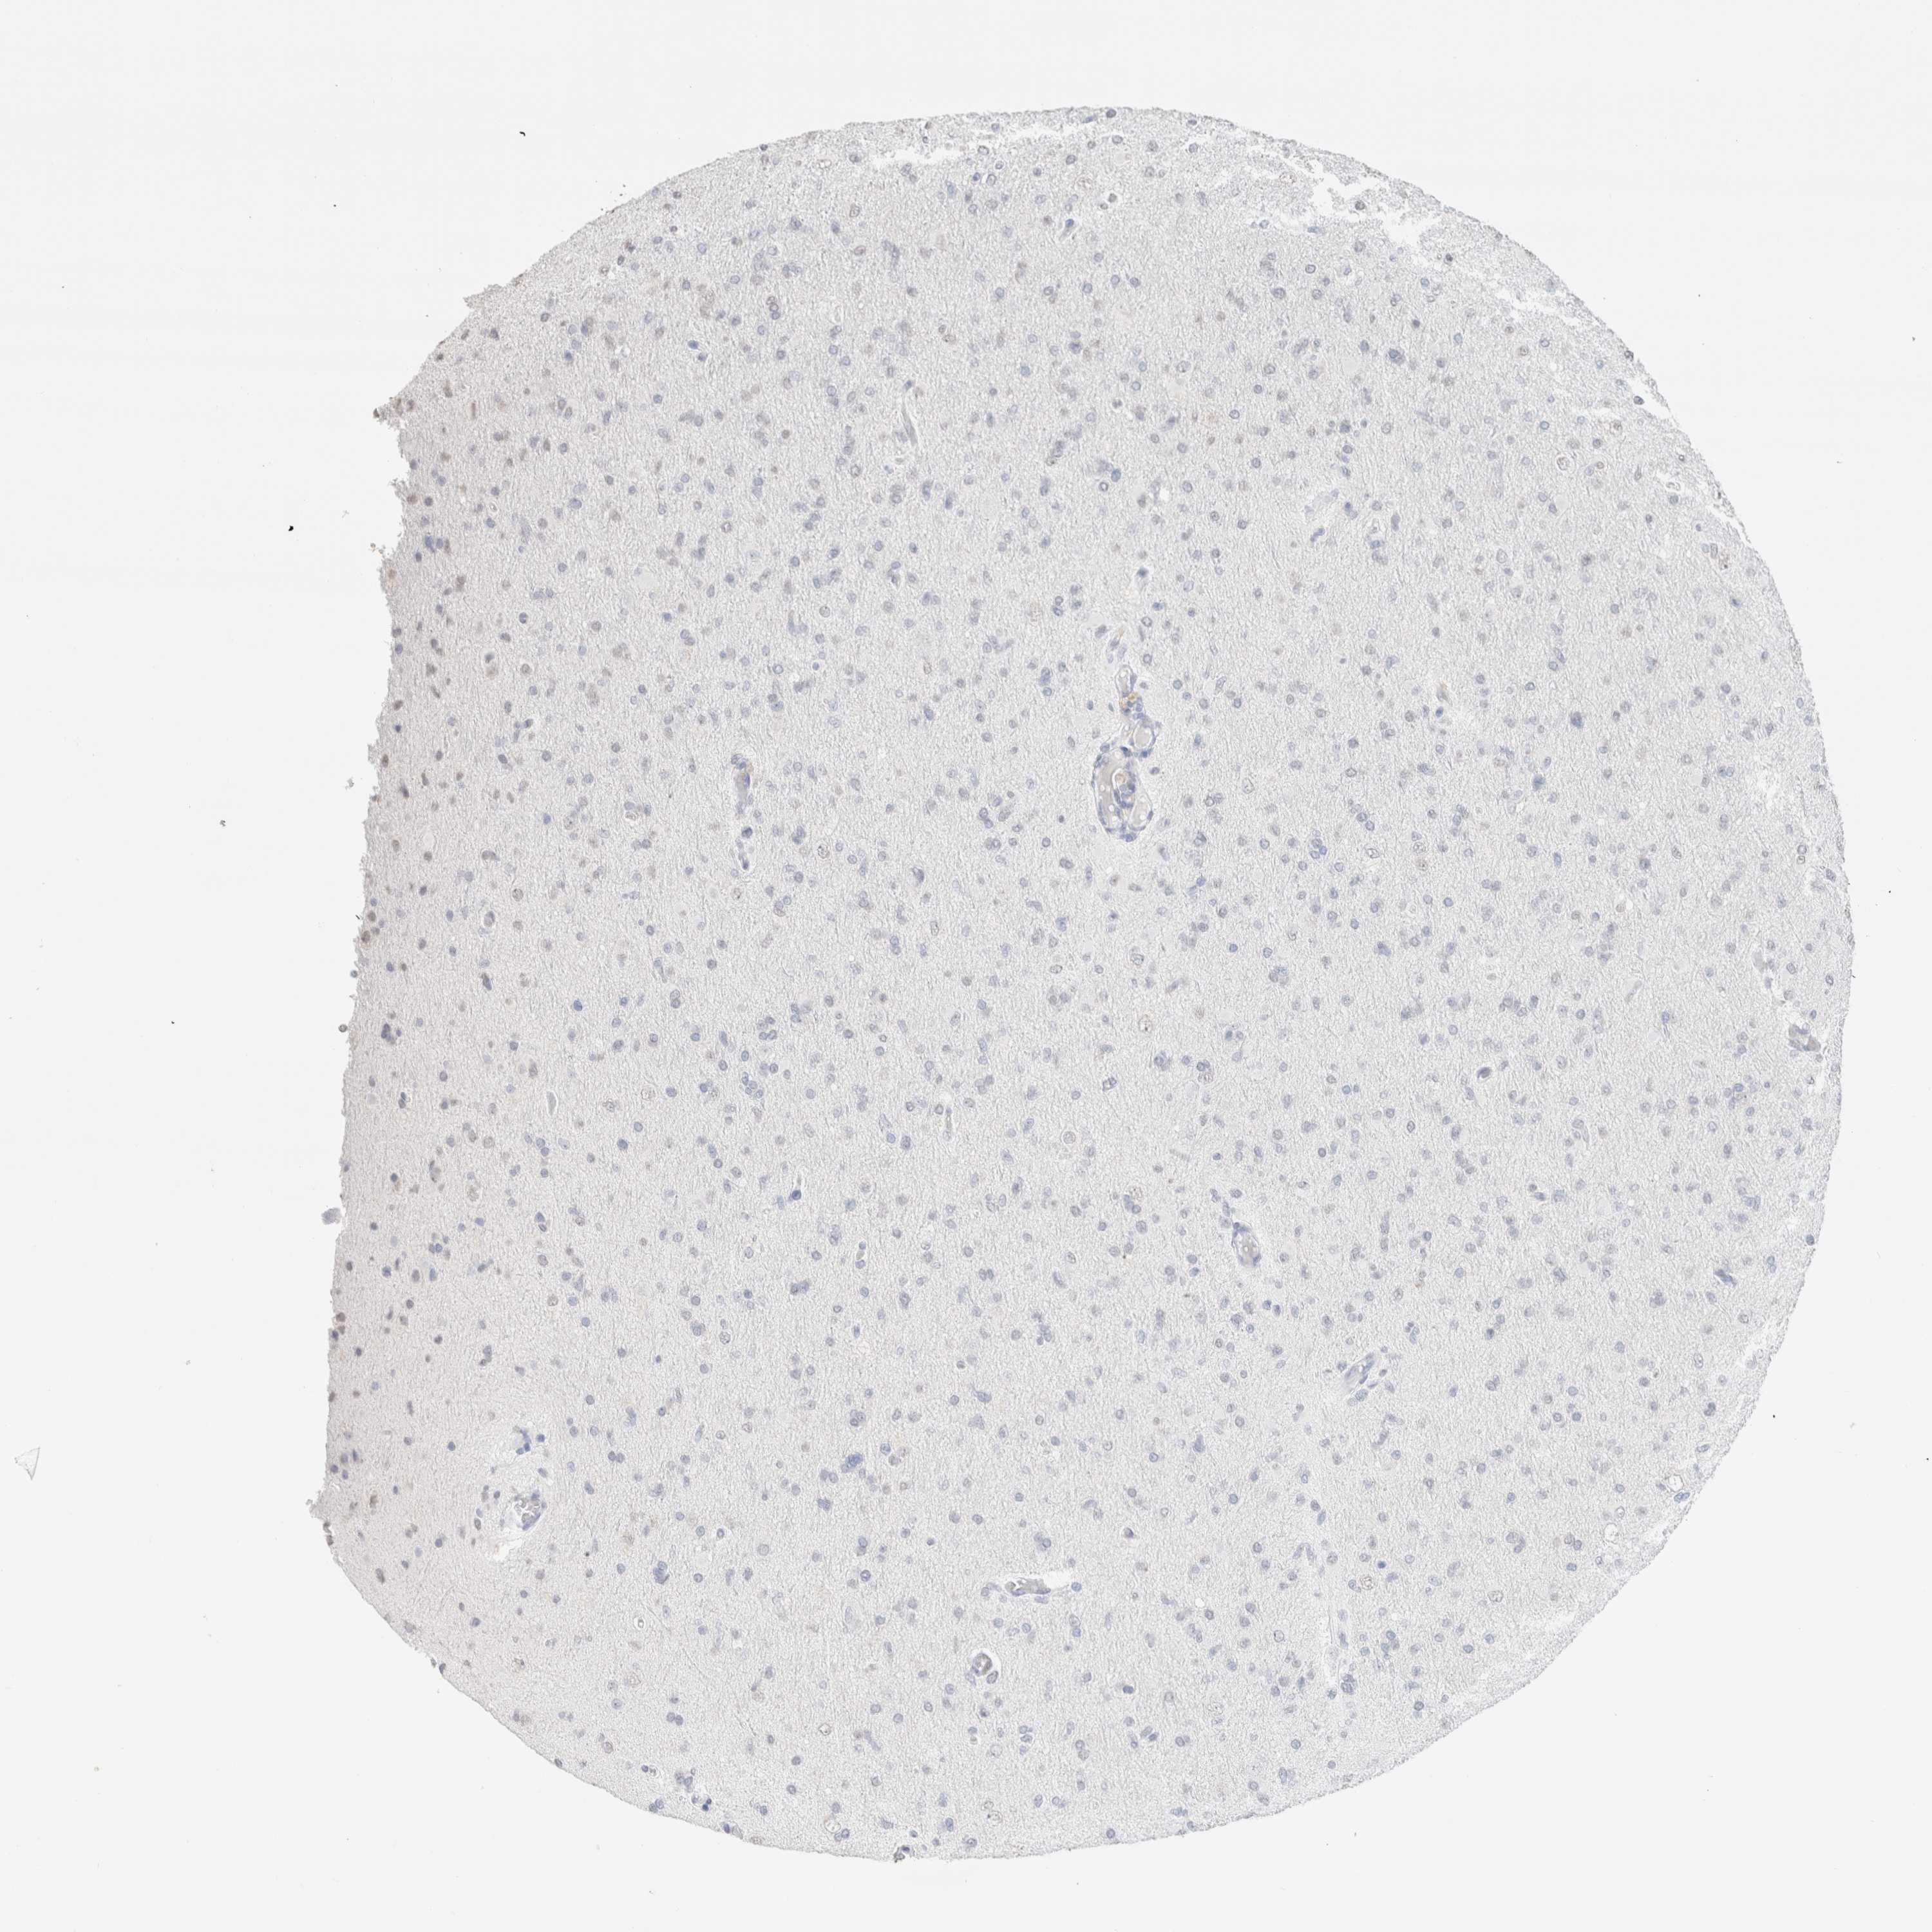

GLIOMA - Protein expressioni

A mouse-over function shows sample information and annotation data. Click on an image to view it in a full screen mode. Samples can be filtered based on level of antibody staining by selecting one or several of the following categories: high, medium, low and not detected. The assay and annotation is described here.

Note that samples used for immunohistochemistry by the Human Protein Atlas do not correspond to samples in the TCGA dataset.

Antibody stainingi

Antibody staining in the annotated cell types in the current human tissue is reported as not detected, low, medium, or high, based on conventional immunohistochemistry profiling in selected tissues. This score is based on the combination of the staining intensity and fraction of stained cells.

Each image is clickable and will lead to virtual microscopy that enables deeper exploration of all samples and also displays staining intensity scores, fraction scores and subcellular localization as well as patient and tissue information for each sample.

Antibody HPA050092

Antibody CAB025368

Glioma, malignant, High grade

Glioma, malignant, Low grade